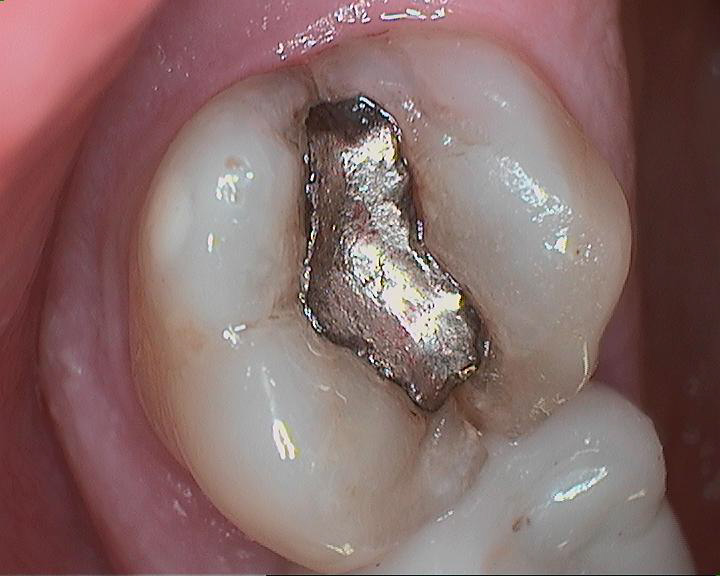

| Top back tooth presents with crack under old filling. |

| Filling was removed without needing to drill. Older silver fillings are not bonded and are only mechanically retained. |